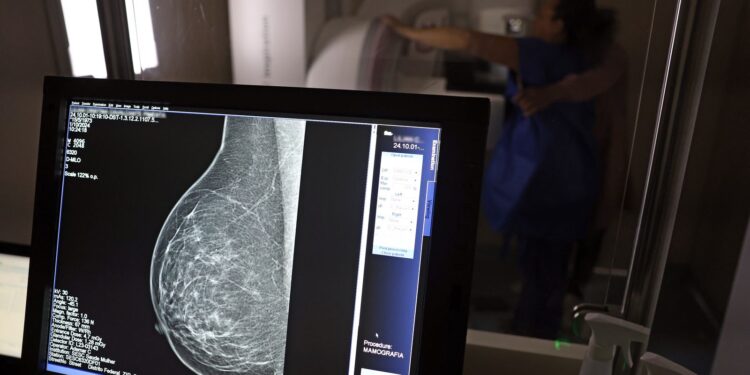

No mês de conscientização sobre o câncer de mama, um relatório destaca a importância de acesso igualitário ao rastreamento e tratamento da doença. Segundo o Atlas da Radiologia no Brasil, do Colégio Brasileiro de Radiologia e Diagnóstico por Imagem (CBR), o acesso aos mamógrafos ainda é um desafio.

O país tem 6.826 equipamentos registrados, sendo 96% em funcionamento. Metade deles está disponível no Sistema Único de Saúde (SUS), responsável por atender 75% da população. Isso equivale a 2,13 mamógrafos por 100 mil habitantes dependentes do SUS.

Na saúde suplementar, que cobre 25% da população, o cenário é mais favorável: 6,54 aparelhos por 100 mil beneficiárias, quase o triplo da rede pública. O Acre exemplifica essa disparidade — são 35,38 mamógrafos por 100 mil habitantes na rede privada, contra 0,84 no SUS.

Há disparidades regionais. Roraima tem a menor proporção (1,53 por 100 mil), seguida do Ceará (2,23) e Pará (2,25). A Paraíba lidera o ranking (4,32), à frente do Distrito Federal (4,26) e do Rio de Janeiro (3,93).

O Brasil tem uma cobertura muito baixa de mamografias: 24%. O ideal recomendado pela Organização Mundial da Saúde é de 70%. Mesmo em lugares como o estado de São Paulo, que tem a maior concentração de mamógrafos do país, a taxa gira em torno de 26%.

Em setembro, o Ministério da Saúde ampliou as diretrizes de rastreamento, recomendando que mulheres entre 40 e 49 anos realizem mamografias, mesmo sem sintomas. De acordo com o Instituto Nacional do Câncer (Imca), mais de 73 mil mulheres recebem o diagnóstico de câncer de mama anualmente no Brasil.